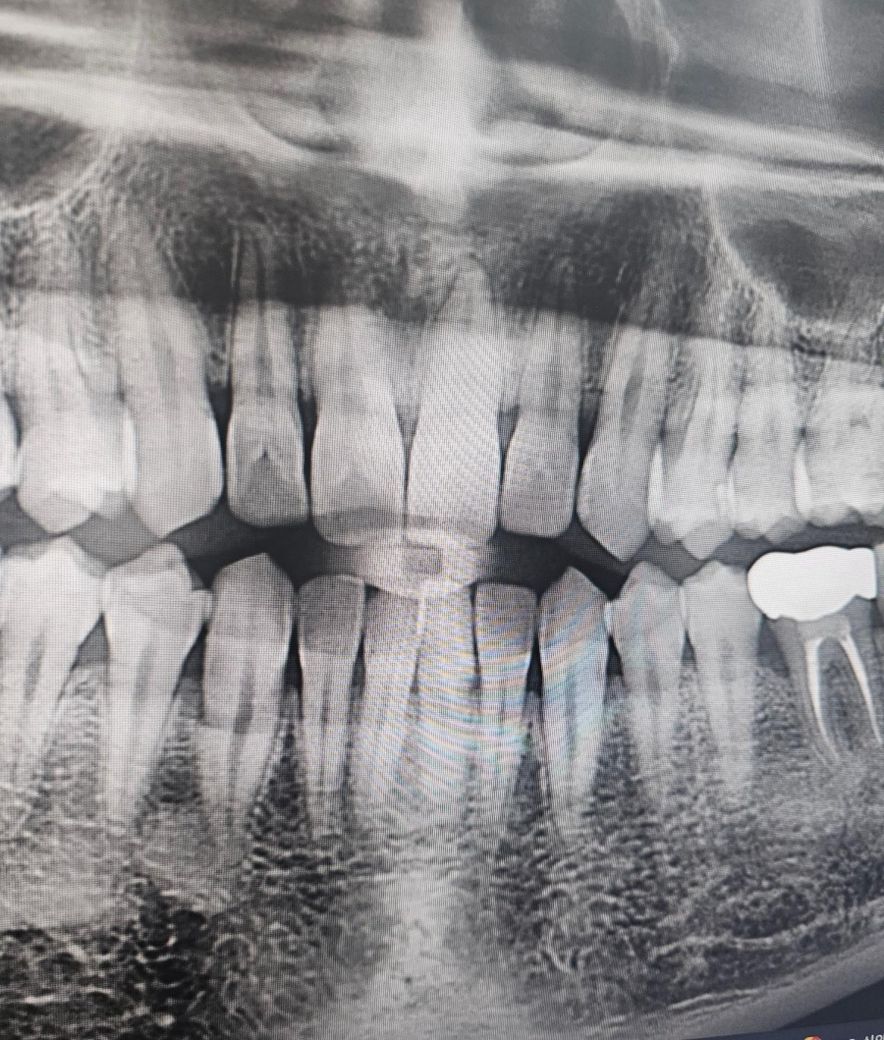

• 3번 째 사진

두번째 치과에서 하신 말씀이랑 다들 비슷한 의견일꺼에요. 치과의사마다 치료 하는 방법이 다르기 때문에 어떤게 옳다고 말씀드리기가 어렵습니다. 사진상으로 인접면에 충치가 없는건 아니고 의심되는 치아들이 많이 보이긴하니 계속해서 의심이 드신다면 불편한 치아만 치료를 먼저 하시고 나머지는 지켜보시면될것같습니다.

사진으로만 보기에는 큰충치가 보이지는 않습니다.

정확한 확인을 위해서는 육안으로도 봐야 알수 있을것으로 생각됩니다.